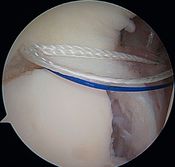

In 1985, Andrews et al. were the first to see, under arthroscopy, superior labral tears (Figure and Video) in 36 throwing athletes (sometimes associated with articular rotator cuff tears).[5]

Articular rotator cuff tears

They reported that simple debridement allowed 85% of athletes to resume their sport at the same level (Figure and Video).

Simple labral debridement